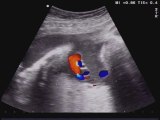

Aloka- Volvolo intestinale

Gerardo Di Meglio

2012-01-24